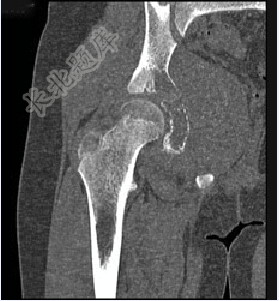

- 单项选择题男,15岁,右髋部疼痛、红肿,有压痛,皮温增高,结合图像,最可能的诊断是( )

A、Ewing肉瘤

B、急性骨髓炎

C、转移性神经母细胞瘤

D、骨肉瘤

E、骨结核